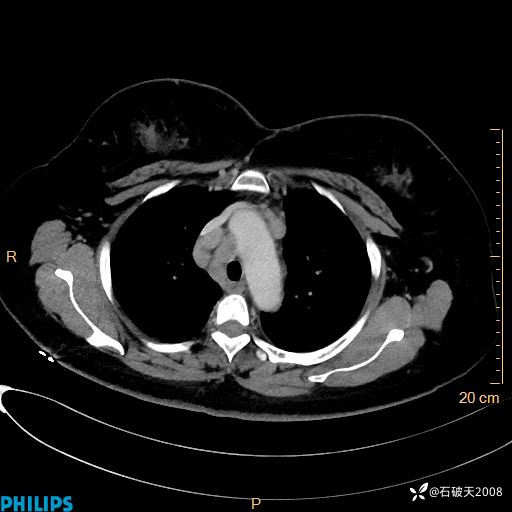

肺窗

动脉期